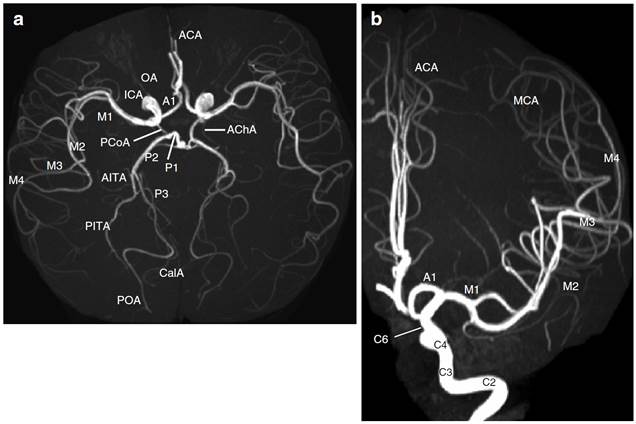

Intracranial vessels

Middle

cerebral artery

(From Neurovascular imaging –

2011)